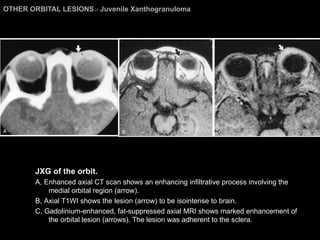

Juvenile Xanthogranuloma Nevoxanthoendothelioma Benign grunulomatous disease of unknown etiology and pathogenesis. Usually  self-healing  disorder of  infants, children , and occasionally adults.  The M/C site is the skin. Orbital involvement with JXG is  rare. M/C sites of orbital involvement = iris and the ciliary body. Imagings: Enhancing soft tissue mass and anterior portion of orbit. Bony wall of the orbit may be involved. Distinguished from LCH radiologically.

OTHER ORBITAL LESIONS >  Juvenile Xanthogranuloma JXG of the orbit.  A, Enhanced axial CT scan shows an enhancing infiltrative process involving the medial orbital region (arrow).  B, Axial T1WI shows the lesion (arrow) to be isointense to brain.  C, Gadolinium-enhanced, fat-suppressed axial MRI shows marked enhancement of the orbital lesion (arrows). The lesion was adherent to the sclera.